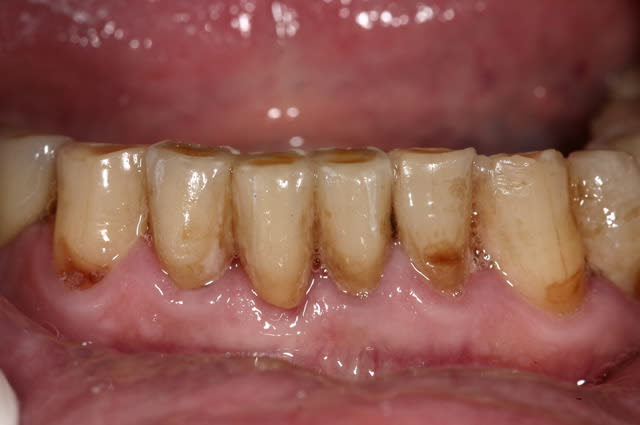

et ici ?? vous feriez quoi ?

32 et 42 pas mobiles

malheureusement, l'espace est réduit pour mettre deux implants.

comment avez vous déjà géré ce type de cas ??

le haut est déjà traité...

Img 0064 fykvs7 - Eugenol

Img 0066 bpmgnj - Eugenol

R2 bcqfqu - Eugenol

Img 0226 iaoqtw - Eugenol

003 penrd2 - Eugenol